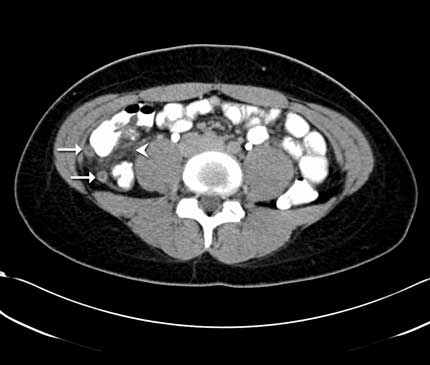

Apendicitis: Una vista transversal de TC a través del abdomen inferior del paciente también corta a través del apéndice hinchado e inflamado en dos sitios (flechas). La inflamación se ha extendido a la grasa intrabdominal cercana (cabeza de flecha). Para más información consulte Apendicitis.

Nota: Las imágenes se muestra para fines ilustrativos. No trate de sacar conclusiones comparando esta imagen con otras en el sitio. Solamente los radiólogos calificados deben interpretar las imágenes.